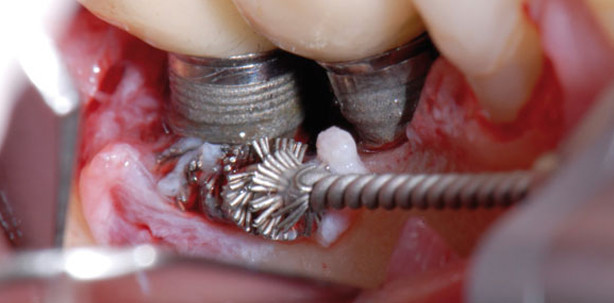

Durch den chirurgischen Zugang wird dem Problem der schlechten Sicht und Erreichbarkeit im Bereich der Implantatwindungen Rechnung getragen. Bevor ein Eingriff mit chirurgischem Zugang geplant wird, sollte analog zur Parodontitistherapie immer erst der Versuch mit den beschriebenen nichtchirurgischen Therapieverfahren gemacht werden. Im Rahmen der Reevaluation kann bei persistierenden Sondierungstiefen über 4 mm, anhaltendem Bleeding on Probing oder anhaltender Suppuration bei einem fortgeschrittenen marginalen Knochenabbau von über 2 mm die Indikation zu einer regenerativen oder resektiven chirurgischen Behandlung gestellt werden. Bei moderater bis fortgeschrittener Periimplantitis ist ein antiinfektiöses OP-Protokoll mit Open Flap Debridement und Dekontamination der Implantatoberfläche unter adjunktiver Antibiotikagabe erfolgreich (Heitz-Mayfield 2012). Nach aktueller Datenlage scheint im Einzelnen folgendes Vorgehen von Vorteil zu sein (Mombelli 2012): Nach Schaffung des chirurgischen Zugangs mit einem Mukoperiostlappen erfolgt eine gewissenhafte Reinigung der Oberflächen. Die grobe mechanische Entfernung des periimplantären entzündlichen Granulationsgewebes kann mit einer Titanbürste (Abb. 7), Küretten oder Ultraschallscaler erfolgen. Daraufhin kann die Implantatoberfläche durch Abwischen mit in steriler Kochsalzlösung oder Antiseptika getränkten Wattepellets, mittels Pulverstrahlgerät (Abb. 8), Laser oder photodynamischer Therapie dekontaminiert werden. Die gereinigten Defekte können mit Knochenersatzmaterial (Abb. 10) gefüllt werden, was für eine Stabilisierung des Defekts sorgt und auch ästhetische Vorteile bietet. Das eingebrachte Material sollte mit einer resorbierbaren Membran abgedeckt werden (Abb. 11). Der regenerative Weg ist vor allem bei 4- oder 3-wandigen Defekten Erfolg versprechend. 1- oder 2-wandige Defekte sollten eher resektiv angegangen werden. Mit einem apikal verschobenen Lappen kann der nicht mehr osseointegrierte Implantatteil der Mundhygiene zugänglich gemacht werden. Unterstützend kann eine Kombination aus Amoxicillin und Metronidazol zur systemischen Verabreichung verschrieben und dem Patienten die Anwendung von CHX-Spülung empfohlen werden. Einer Untersuchung von Claffey zufolge ist davon auszugehen, dass mit einem Zugangslappen und systemischer Antibiotikagabe etwa 60 Prozent der Läsionen zum Stillstand gebracht werden (Claffey et al. 2008). Eine komplette Defektauffüllung nach gesteuerter Knochenregeneration kann jedoch nur in etwa 10 Prozent der Fälle erwartet werden (Sahrmann et al. 2011).